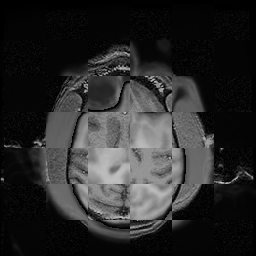

For each of the 10 subjects, we show checkerboard slices in each direction (1) before registration, first row; (2) after rigid->scaleversor->affine registration, second row; and (3) after BSpline registration, third row.

Marc